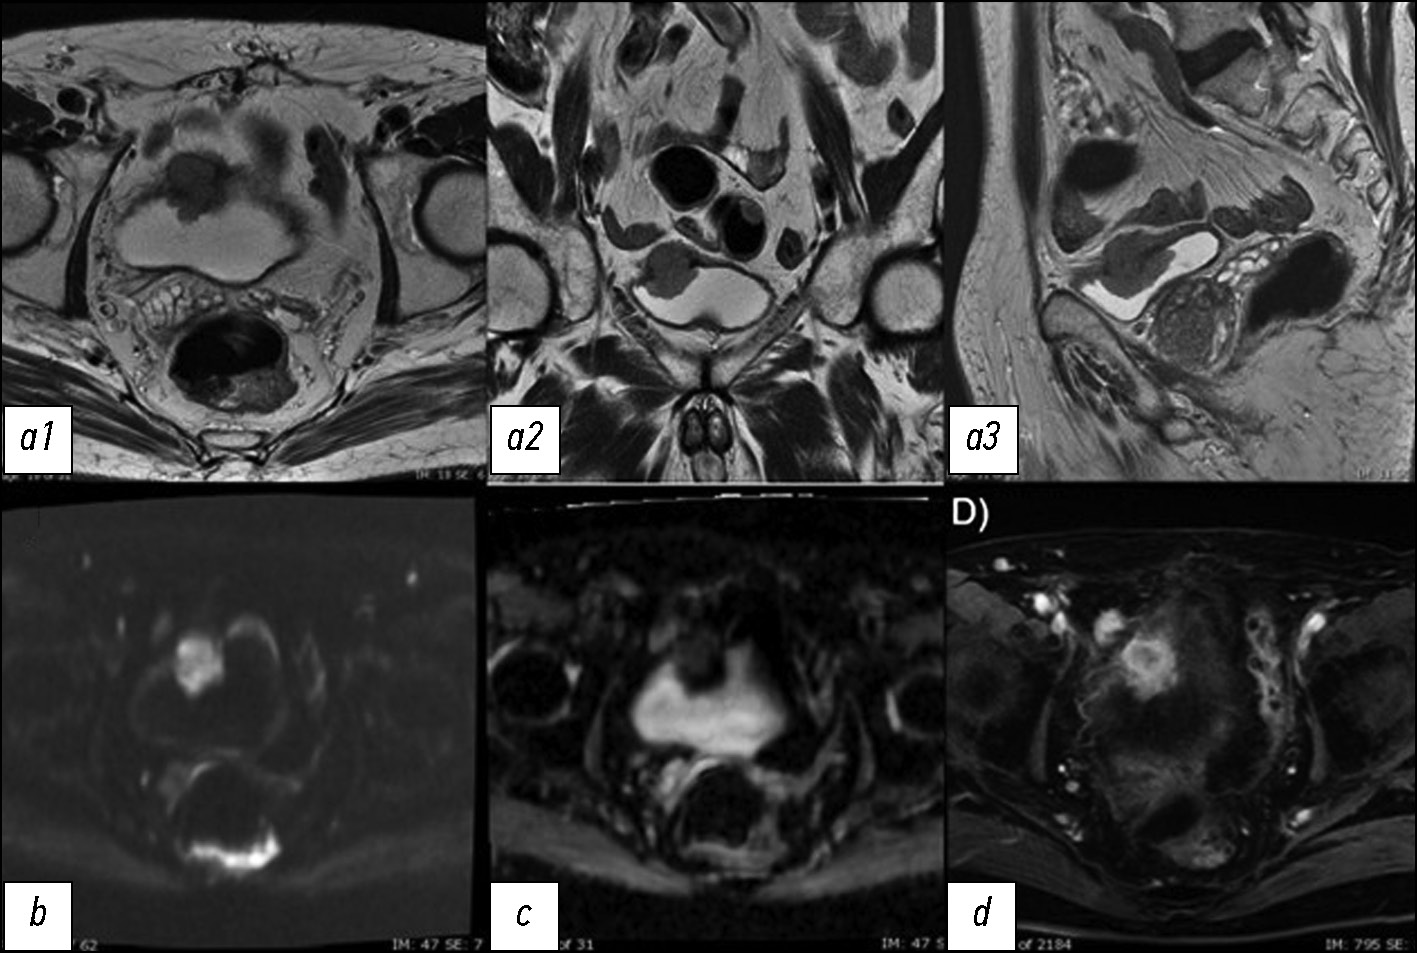

The development of the vesical imaging-reporting and data system (VI-RADS) score helps standardize the approach to MRI acquisition, interpretation, and reporting in patients diagnosed with BCa through TURBT. The score ranges from 1 to 5 and expresses the increasing risk of invasion of the detrusor muscle [6]. For accurate examination, the sequences include T2W, DWI/ADC, and DCE with each sequence generating a score of 1–5. T1W is not useful for differentiating MIBC from NMIBC because the detrusor muscle shows intermediate-signal intensity as well as a cancerous process [23].

Initially, the structural information in the T2W must be analyzed, evaluating the integrity of the muscular layer in T2W that should appear as homogeneously hypointense in contrast with a hyperintense signal of the bladder content. Then, the signal on DWI/ADC and DCE sequences must be evaluated. In tumors, the signal would appear hyperintense on DWI and hypointense on the ADC map, and there is an early enhancement of the inner layer. After obtaining information from each sequence, the combination of the different scores is compared to obtain the final VI-RADS score.

VI-RADS 1 is assigned when there is an interruption of the intensity signal line corresponding to the muscular layer in T2W. The maximum size reached from the lesion (sessile or vegetating) is 1 cm. VI-RADS 1 suggests an NMIBC.

VI-RADS 2 is assigned when there is an interruption of the intensity signal line but with a diameter >1 cm. The lesion could be associated with edema, appearing with a thickening line, and related to an increasing probability of invasion. VI-RADS 3 expresses a doubt: there is no clear disruption of the low-signal intensity of the muscular layer in T2W. VI-RADS 4 is assigned when there is a certain invasion of the muscular layer. VI-RADS 5 is assigned when the muscular layer invasion is associated with the involvement of the nearly adipose tissue.

In case of a discrepancy in results, the DWI/ADC map and DCE will prevail to downgrade and upgrade lesions [5].

In conclusion, MRI is rapidly becoming a leading imaging modality in BCa diagnostic workup, assessment of response to therapies, and longitudinal surveillance and plays an important role in treatment planning for BCa surgical and radiation therapy. Nevertheless, transurethral resection biopsy is required for tumor grading and cannot be replaced by MRI (Fig. 5 and 6).

Fig. 5. (a) Multiplanar T2W sequences showing a mass on the left posterior wall, >1 cm in size, with an intermediate signal of the muscular layer (VI-RADS 4). (b) DWI sequence and ADC maps showing a lesion with significantly limited diffusion, extending through the muscular layer. The low ADC value of approximately 0.9 × 10−3 mm2/sec denote malignancy (VI-RADS 4). (c, d) DCE sequence showing early and heterogeneous enhancement of the lesion, extending through the muscular layer (VI-RADS 4). The VI-RADS overall score was four. Image source: Eusebi Laura, Masino Federica, Gifuni Rossella, Fierro Davide, Michele Bertolotto, Cova Maria Assunta, Giuseppe Guglielmi. Role of Multiparametric-MRI in Bladder Cancer. Current Radiology Reports 11, 69–80 (2023). https://doi.org/10.1007/s40134-023-00412-5. This article is an open access article distributed under the terms and conditions of the Creative Commons Attribution (CC BY) license 4.0 (http://creativecommons.org/licenses/by/4.0/).

Fig. 6. (a) Multiplanar T2W sequences showing a mass, >1 cm, on the right lateral wall of the bladder dome, with an intermediate signal extending through the muscular layer and invading the perivesical adipose tissue (VI-RADS 5). (b) DWI sequence and c ADC map showing a significantly limited diffusion lesion extending through the muscular layer and invading the perivesical adipose tissue (VI-RADS 5). (c) DCE showing an early and heterogeneous improvement of the lesion extending through the muscular layer and the perivesical adipose tissue (VI-RADS 5). The VI-RADS overall score was five. Image source: Eusebi Laura, Masino Federica, Gifuni Rossella, Fierro Davide, Michele Bertolotto, Cova Maria Assunta, Giuseppe Guglielmi. Role of Multiparametric-MRI in Bladder Cancer. Current Radiology Reports 11, 69–80 (2023). https://doi.org/10.1007/s40134-023-00412-5. This article is an open access article distributed under the terms and conditions of the Creative Commons Attribution (CC BY) license 4.0 (http://creativecommons.org/licenses/by/4.0/).